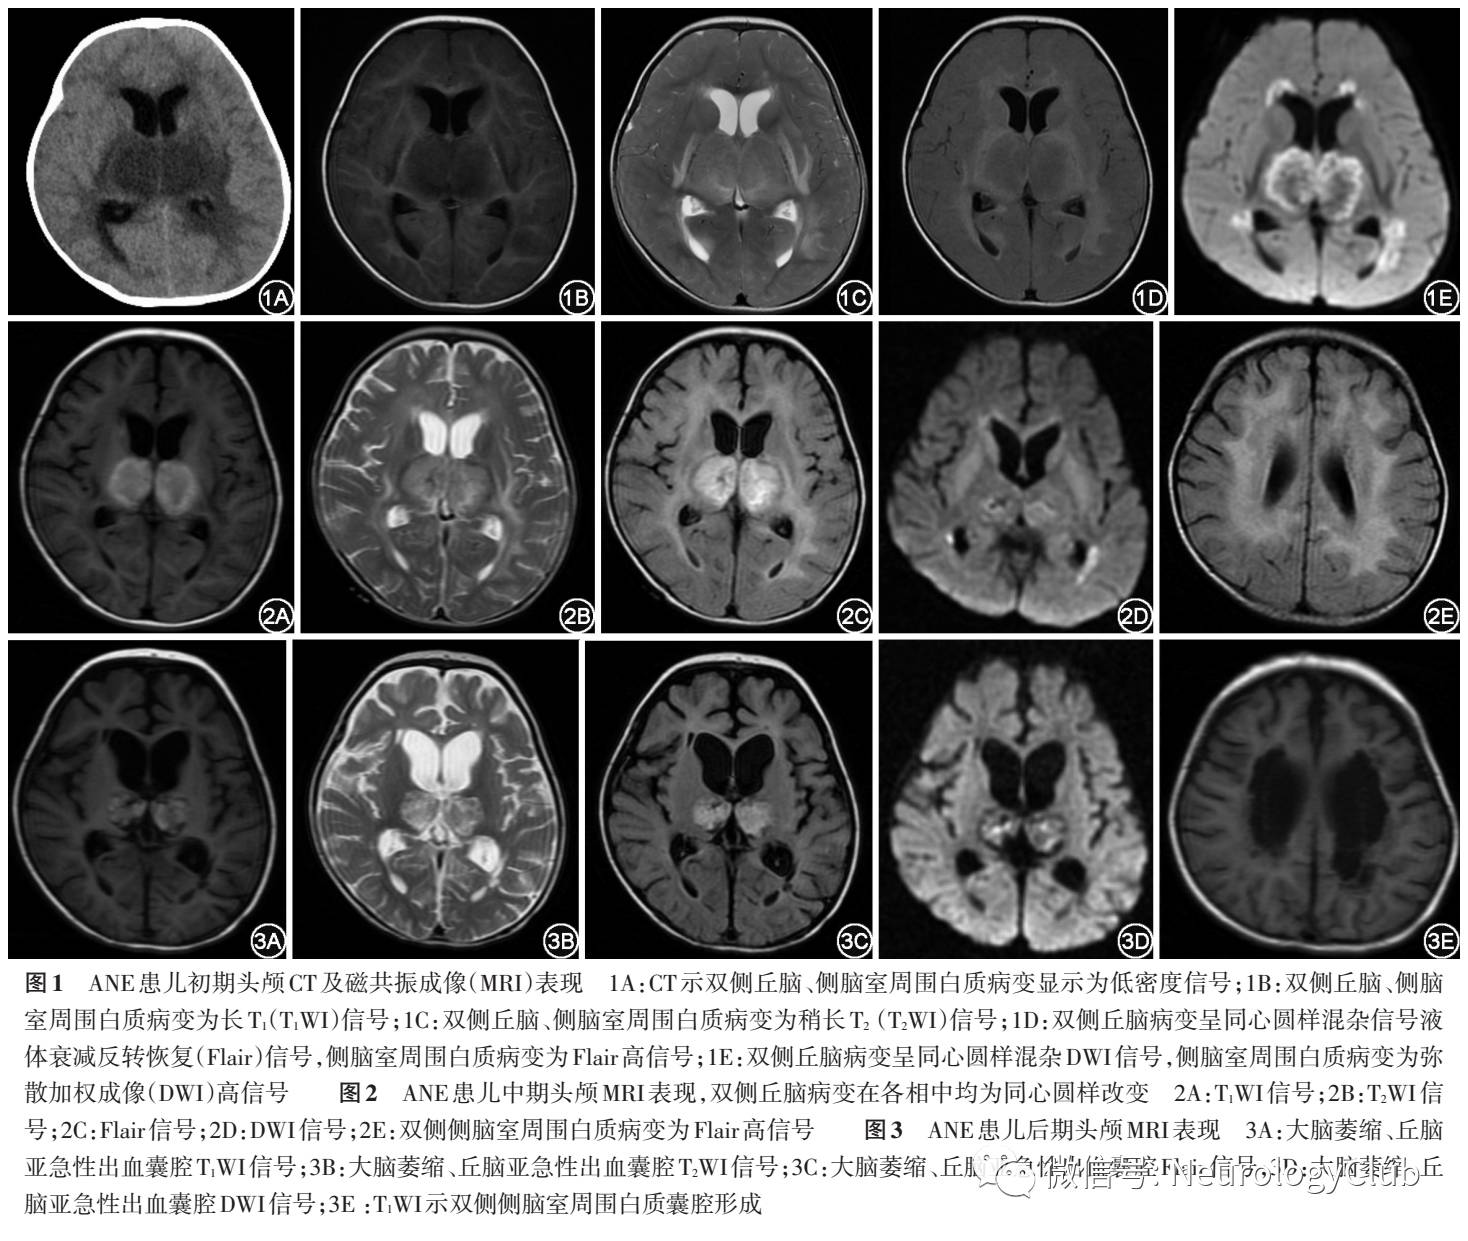

(1)CT和MRIANE的初期影像改变病变部位主要表现为脑水肿,病灶在脑头颅CT上(图1)表现为低密度信号。头颅MRI(图1)病灶为长T1长T2,液体衰减反转恢复(Flair)和弥散加权成像(DWI)为高信号,灰质病灶可以为同心圆样的混杂信号

ANE的中期影像改变病变主要表现为点状出血、坏死。在头颅CT上表现杂色,为花斑状低密度区中掺杂不规则高密度影,脑白质密度更低。头颅MRI(图2):灰质病灶(主要是丘脑)在T1、T2、Flair、DWI均可见同心圆样环状表现。T1:中心低信号,周围环状高信号为亚急性出血改变;T2:之前的高信号有所减低,周围环绕高信号或等信号,小点状出血在T2通常是模糊的。Flair:高信号更加明显,中心及外周均混杂有低信号。DWI:混杂信号,高信号较前减少。脑白质始终是长T1长T2,Flair高信号。

ANE的恢复期影像改变少数轻型病例病灶可完全消失,大部分病例病灶表现为萎缩、含铁血黄素沉积、囊腔形成等退行性改变,在头颅CT及MRI均会留下囊腔形成或大脑萎缩等异常信号,部分病例亚急性出血囊腔形成等异常信号持续存在数月至数年,MRI表现见图3。

经典ANE神经影像特点(图4)为“同心圆、三色板模式或靶样形状”,这种典型改变因为没有T2穿透效应的限制,在头颅MRI的表观弥散系数(ADC)图上尤为明显。病变中央部显示为略高信号,周围病变为低信号(表示细胞毒性水肿),损害灶的外围部有比中央更高的信号(表示血管源性水肿)。ANE的病理改变可解释上诉神经影像学改变。通常,病变的中心是血管周围出血、神经元坏死和神经胶质细胞增生,ADC显示略高信号;在中心的外围部分显示低信号,为动脉、静脉及毛细血管淤血和少突胶质细胞急性水肿;最外层的高信号为病变的渗出,即血管源性水肿值得注意的是典型的病变主要出现在灰质,特别是在双侧丘脑